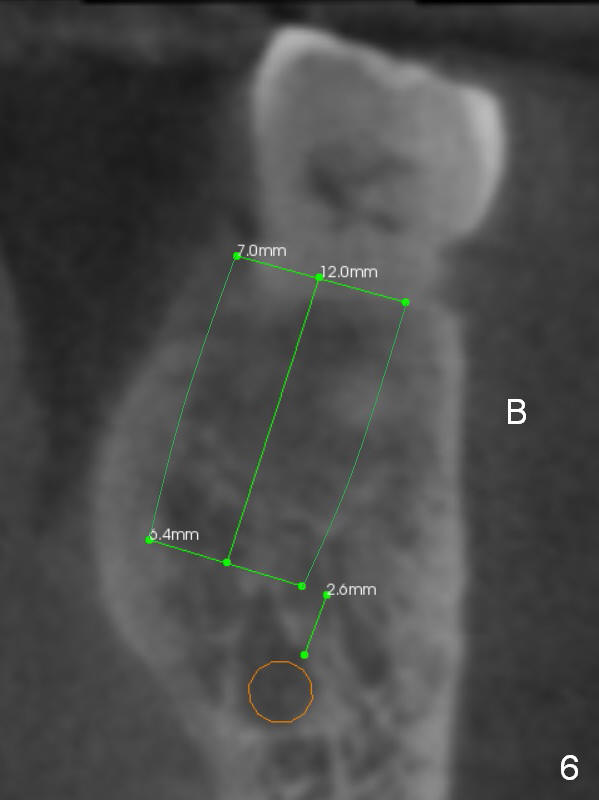

A 71-year-old man (CK) has pain in mastication when the upper left implant treatment is finished. The tooth #19 with distal caries (Fig.1 (CT sagittal section) *) seems to be non-salvageable. The mesial (M) and distal (D) roots appear to be large and closer to the root of the tooth #20 than that of #18. A large implant (7x12 mm) placed in the middle of the socket may increase the chance to invade the root of #20 (Fig.2, 4 (axial section)), as compared to that placed more distal (Fig.3,5).

The shorter implant (10 mm (Fig.7 (coronal section)). as compared to 12 mm (Fig.6) more or less placed in the middle of the septum may decrease the chance to penetrate the coronal extension (Fig.8 brown triangle) of the Inferior Alveolar Canal (brown circle).